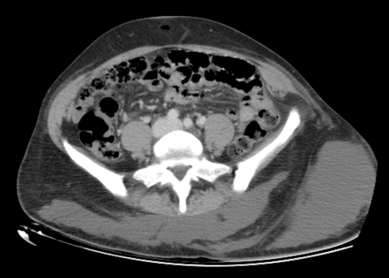

No es un simple hematoma

Mariana Invernizzi, Silvana Lapi, Mario Almada, Virginia Rodríguez, Eduardo Olivera

ecir.urug.10.1.4